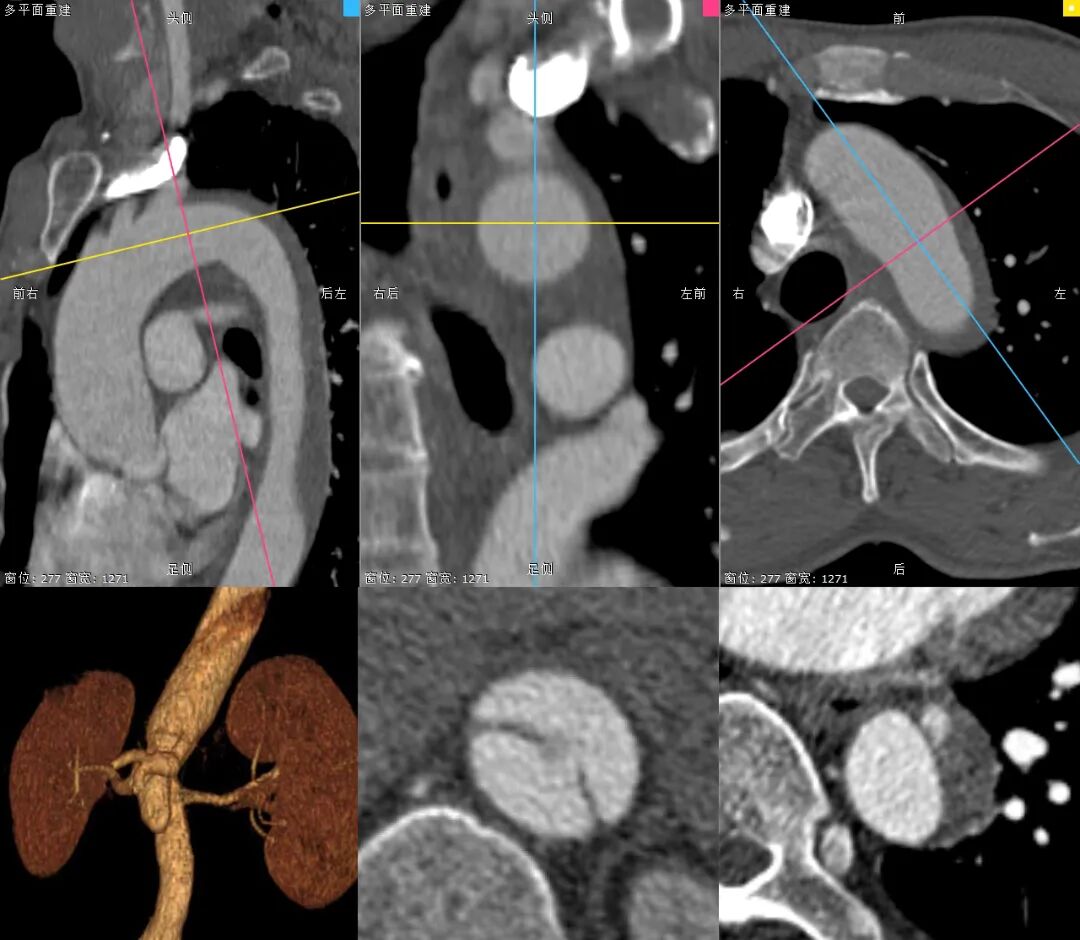

主动脉CTA详解:Standford B型主动脉夹层,破口位于胸降主动脉,破口直径7mm,假腔位于真腔前缘;主动脉管壁周围少许渗出影,可见壁内血肿、血栓、溃疡突起,近端血肿已累及LSA根部,LSA与LCCA距离仅8.5mm,左椎动脉优势;弓上三分支血流显影可,内脏区腹腔干动脉、肠系膜上动脉及右肾动脉起自假腔,左肾动脉起自真腔。

Stanford B型主动脉夹层,破口大,位于降主动脉,真腔小,假腔大,对输送系统的稳定性、通过性和柔韧性,要求均较高。

主动脉管壁壁内血肿已累及LSA根部,近端锚定区明显不足, 且LCCA距离LSA不足10mm,需向近端扩展锚定区,重建LSA。

LSA与主动脉弓成锐角,且开口处粗大,呈“火山口”形态,为术中原位开窗角度控制带来难点,且市面常见覆膜支架,开窗难度较大。